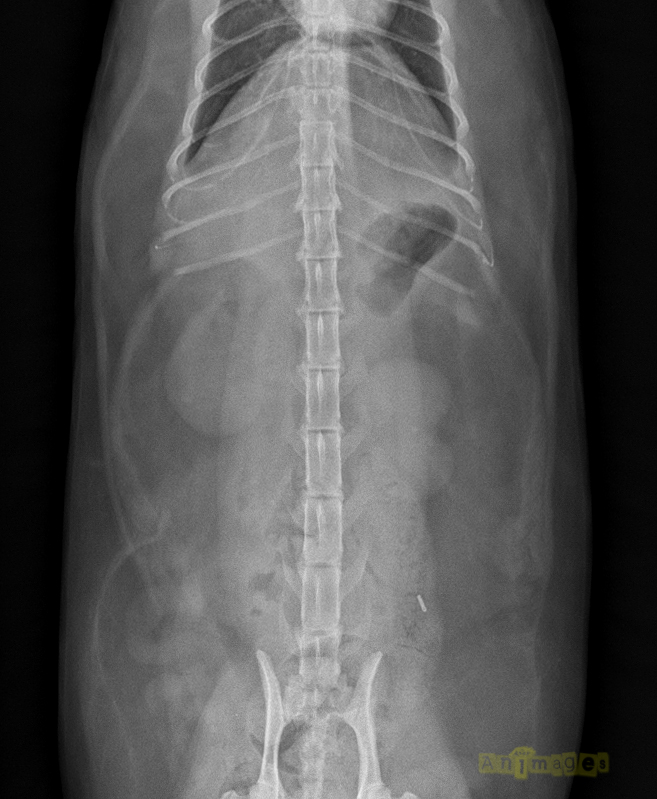

VD